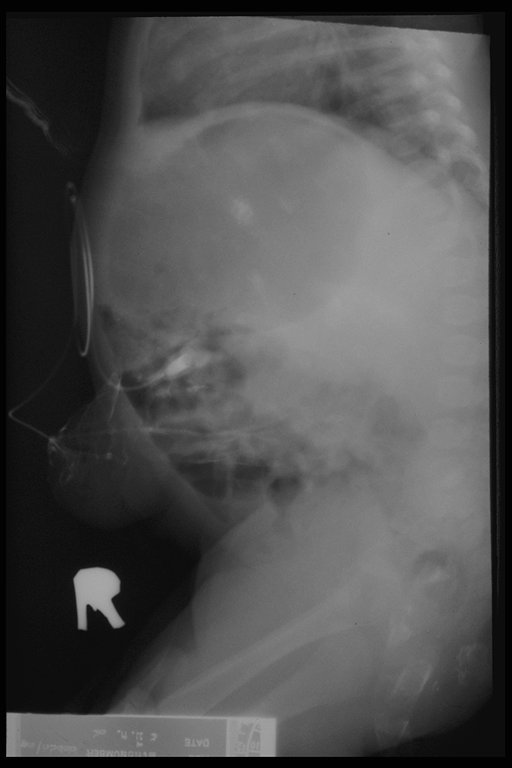

Fistulogram in a child with umbilical hernia and fistula demonstrates the connection to the intestine

Fistulogram demonstrated the tract connected between the umbilicus and the intestine